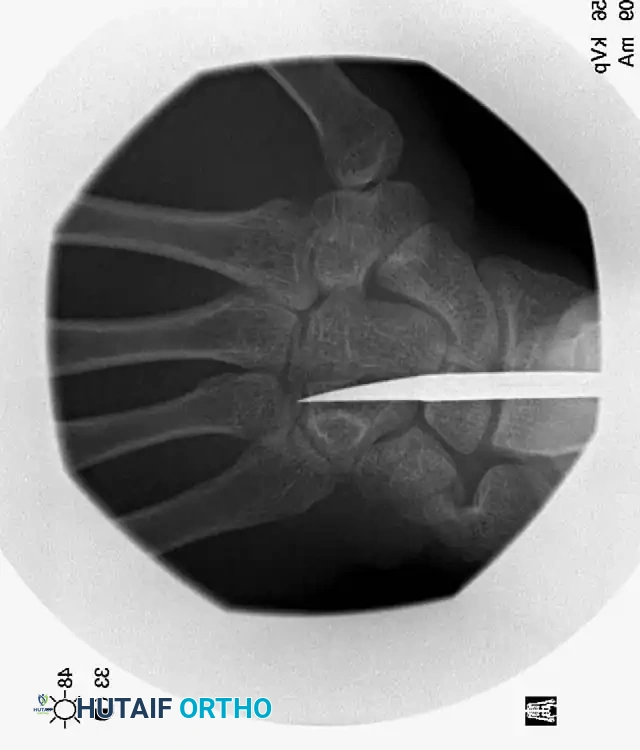

Radiographic Evaluation

Standard posteroanterior (PA) radiographs may appear deceptively benign. The hallmark of a CMC dislocation on a PA view is the loss of the parallel joint surfaces (the "M" line) at the carpometacarpal articulations.

A true lateral radiograph is an absolute necessity for accurate diagnosis, as it will clearly demonstrate the dorsal or volar displacement of the metacarpal bases relative to the carpal row.

Oblique views further delineate the extent of articular comminution and subluxation.

When identified acutely, manual reduction via longitudinal traction and direct pressure over the metacarpal bases is often easily achieved. However, the injury is inherently unstable.

Kirschner wire (K-wire) fixation is almost universally required to prevent redislocation.